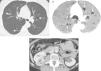

We report the case of a 56-year-old woman, non-smoker, recently diagnosed with breast cancer, who underwent a chest and abdomen computed tomography (CT) as part of her staging study. Multiple pulmonary cysts with a fine, well-defined wall were unexpectedly detected on the CT (Fig. 1A and B), along with a mass in the right kidney containing foci of fatty attenuation (Fig. 1C), consistent with angiomyolipoma (AML). The pulmonary parenchyma interposed between the pulmonary cysts was rigorously normal. In view of these findings, the patient was given a diagnosis of pulmonary lymphangioleiomyomatosis (PLAM).

(A) Axial image of chest CT (pulmonary parenchymal window) showing multiple cysts in both lungs (arrows). Note the normal radiological appearance of the pulmonary parenchyma interposed between the cysts. (B) Minimum intensity projection (minIP) axial reconstruction of chest CT (pulmonary parenchymal window) showing multiple cysts in both lungs (arrows). (C) Axial CT image of the abdomen, showing a mass (black asterisk) in the right kidney (RD) with an area of fatty density (white asterisk), consistent with angiomyolipoma.